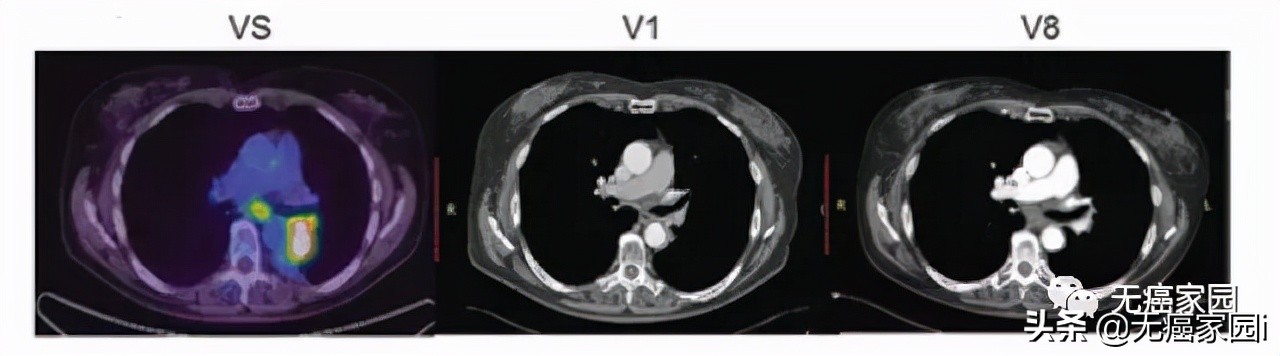

接下来,小编展示联合疗法中一个典型的成功案例,如图所示: 治疗1~2个月后复查,肺部肿瘤完全消失,并且疗效已经保持了18个月。